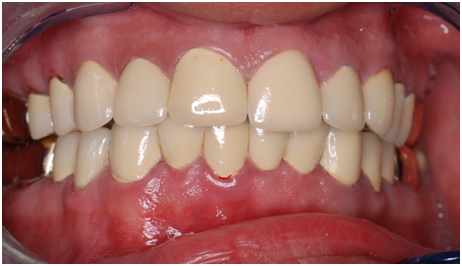

Figure 15 Final frontal view.

Figure 16 Final front view.

Esthetic, phonetics and occlusion were checked after cementation the temporary crowns with temporary (Pro. Temp) luting agent. To avoid any functional problems, the patient was instructed to give the temporaries a period of trial for 2 weeks. Intra occlusal relationship was repeated at this stage again. When the patient reported no discomfort, the final crowns were constructed. Final crowns were cemented using resin composite (Rely X Unicem) luting agent. Teeth restored were # 2, 3, 4, 5, 6, 7, 8, 9,10, 11, 12, 13, 14, 15,18, 19, 20, 21, 22, 23, 24, 25, 26, 27, 28, 29, 30 and 31. Postoperative pictures, x-rays, and impressions were taken (Figure 9−19). The case had a good prognosis considering the patient, good general health and proper attitude toward his oral hinging reported during the maintenance and treatment phases. The periodontium is in functional health status, using gold alloys to restore posterior teeth as well as porcelain-fused to metal crowns to restore anterior teeth conserve tooth structures by minimizing the amount of tooth structure to be cut.